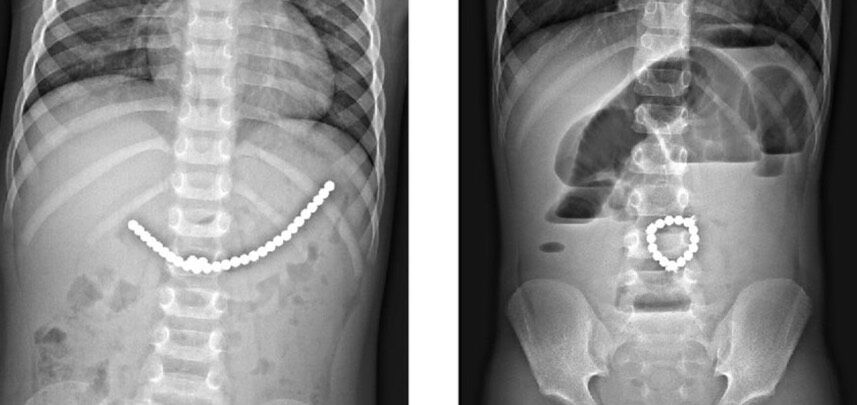

جراحان نیوزلندی طی یک عمل اضطراری موفق شدند حدود ۱۰۰ آهنربای نئودیمیومی فوققوی را از روده یک نوجوان ۱۴ ساله خارج کنند. این نوجوان که پس از بلعیدن چندین آهنربا دچار درد شدید شکم، خونریزی و انسداد روده شده بود، تنها با انجام جراحی نجات پیدا کرد.

پسر نوجوان درباره انگیزه خود توضیح داد: «ویدیوهایی در اینترنت دیدم که بچهها آهنرباها را به لب و زبانشان میچسباندند و میگفتند حس عجیبی دارد. من هم فقط میخواستم بدانم داخل بدنم چه حسی دارد… اما هرگز فکر نمیکردم اینقدر خطرناک باشد.» پزشکان افزودند که آهنرباها در روده به هم چسبیده و باعث فشار شدید، نکروز بافت و آسیب جدی به بخشهایی از روده شدهاند. بخشی از روده نوجوان نیز برای نجات جان او برداشته شد.